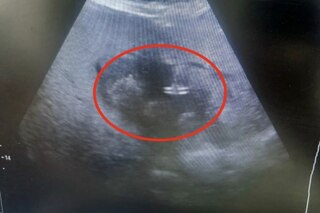

В публикации сказано, что в гнойное хирургическое отделение Балаковской городской клинической больницы поступила 83-летняя пациентка, переведенная из нефрологического отделения. У неё диагностировали обширный абсцесс печени размером около 10 сантиметров, выявленный после двух недель высокой температуры и недомогания.

«Учитывая преклонный возраст пациентки и сопутствующие риски, традиционное полостное оперативное вмешательство было сопряжено с высокой опасностью. Врачам БГКБ удалось избежать обширной операции. Было выполнено малоинвазивное дренирование абсцесса печени под контролем ультразвуковой навигации. Эта методика позволяет с ювелирной точностью ввести дренаж в полость гнойника, минимизируя травматизацию тканей и ускоряя восстановление.

Пациентка успешно перенесла вмешательство под наркозом. Сейчас её состояние стабильно, отмечается положительная динамика: она уже активна — встает, сидит, двигается», — говорится в публикации.